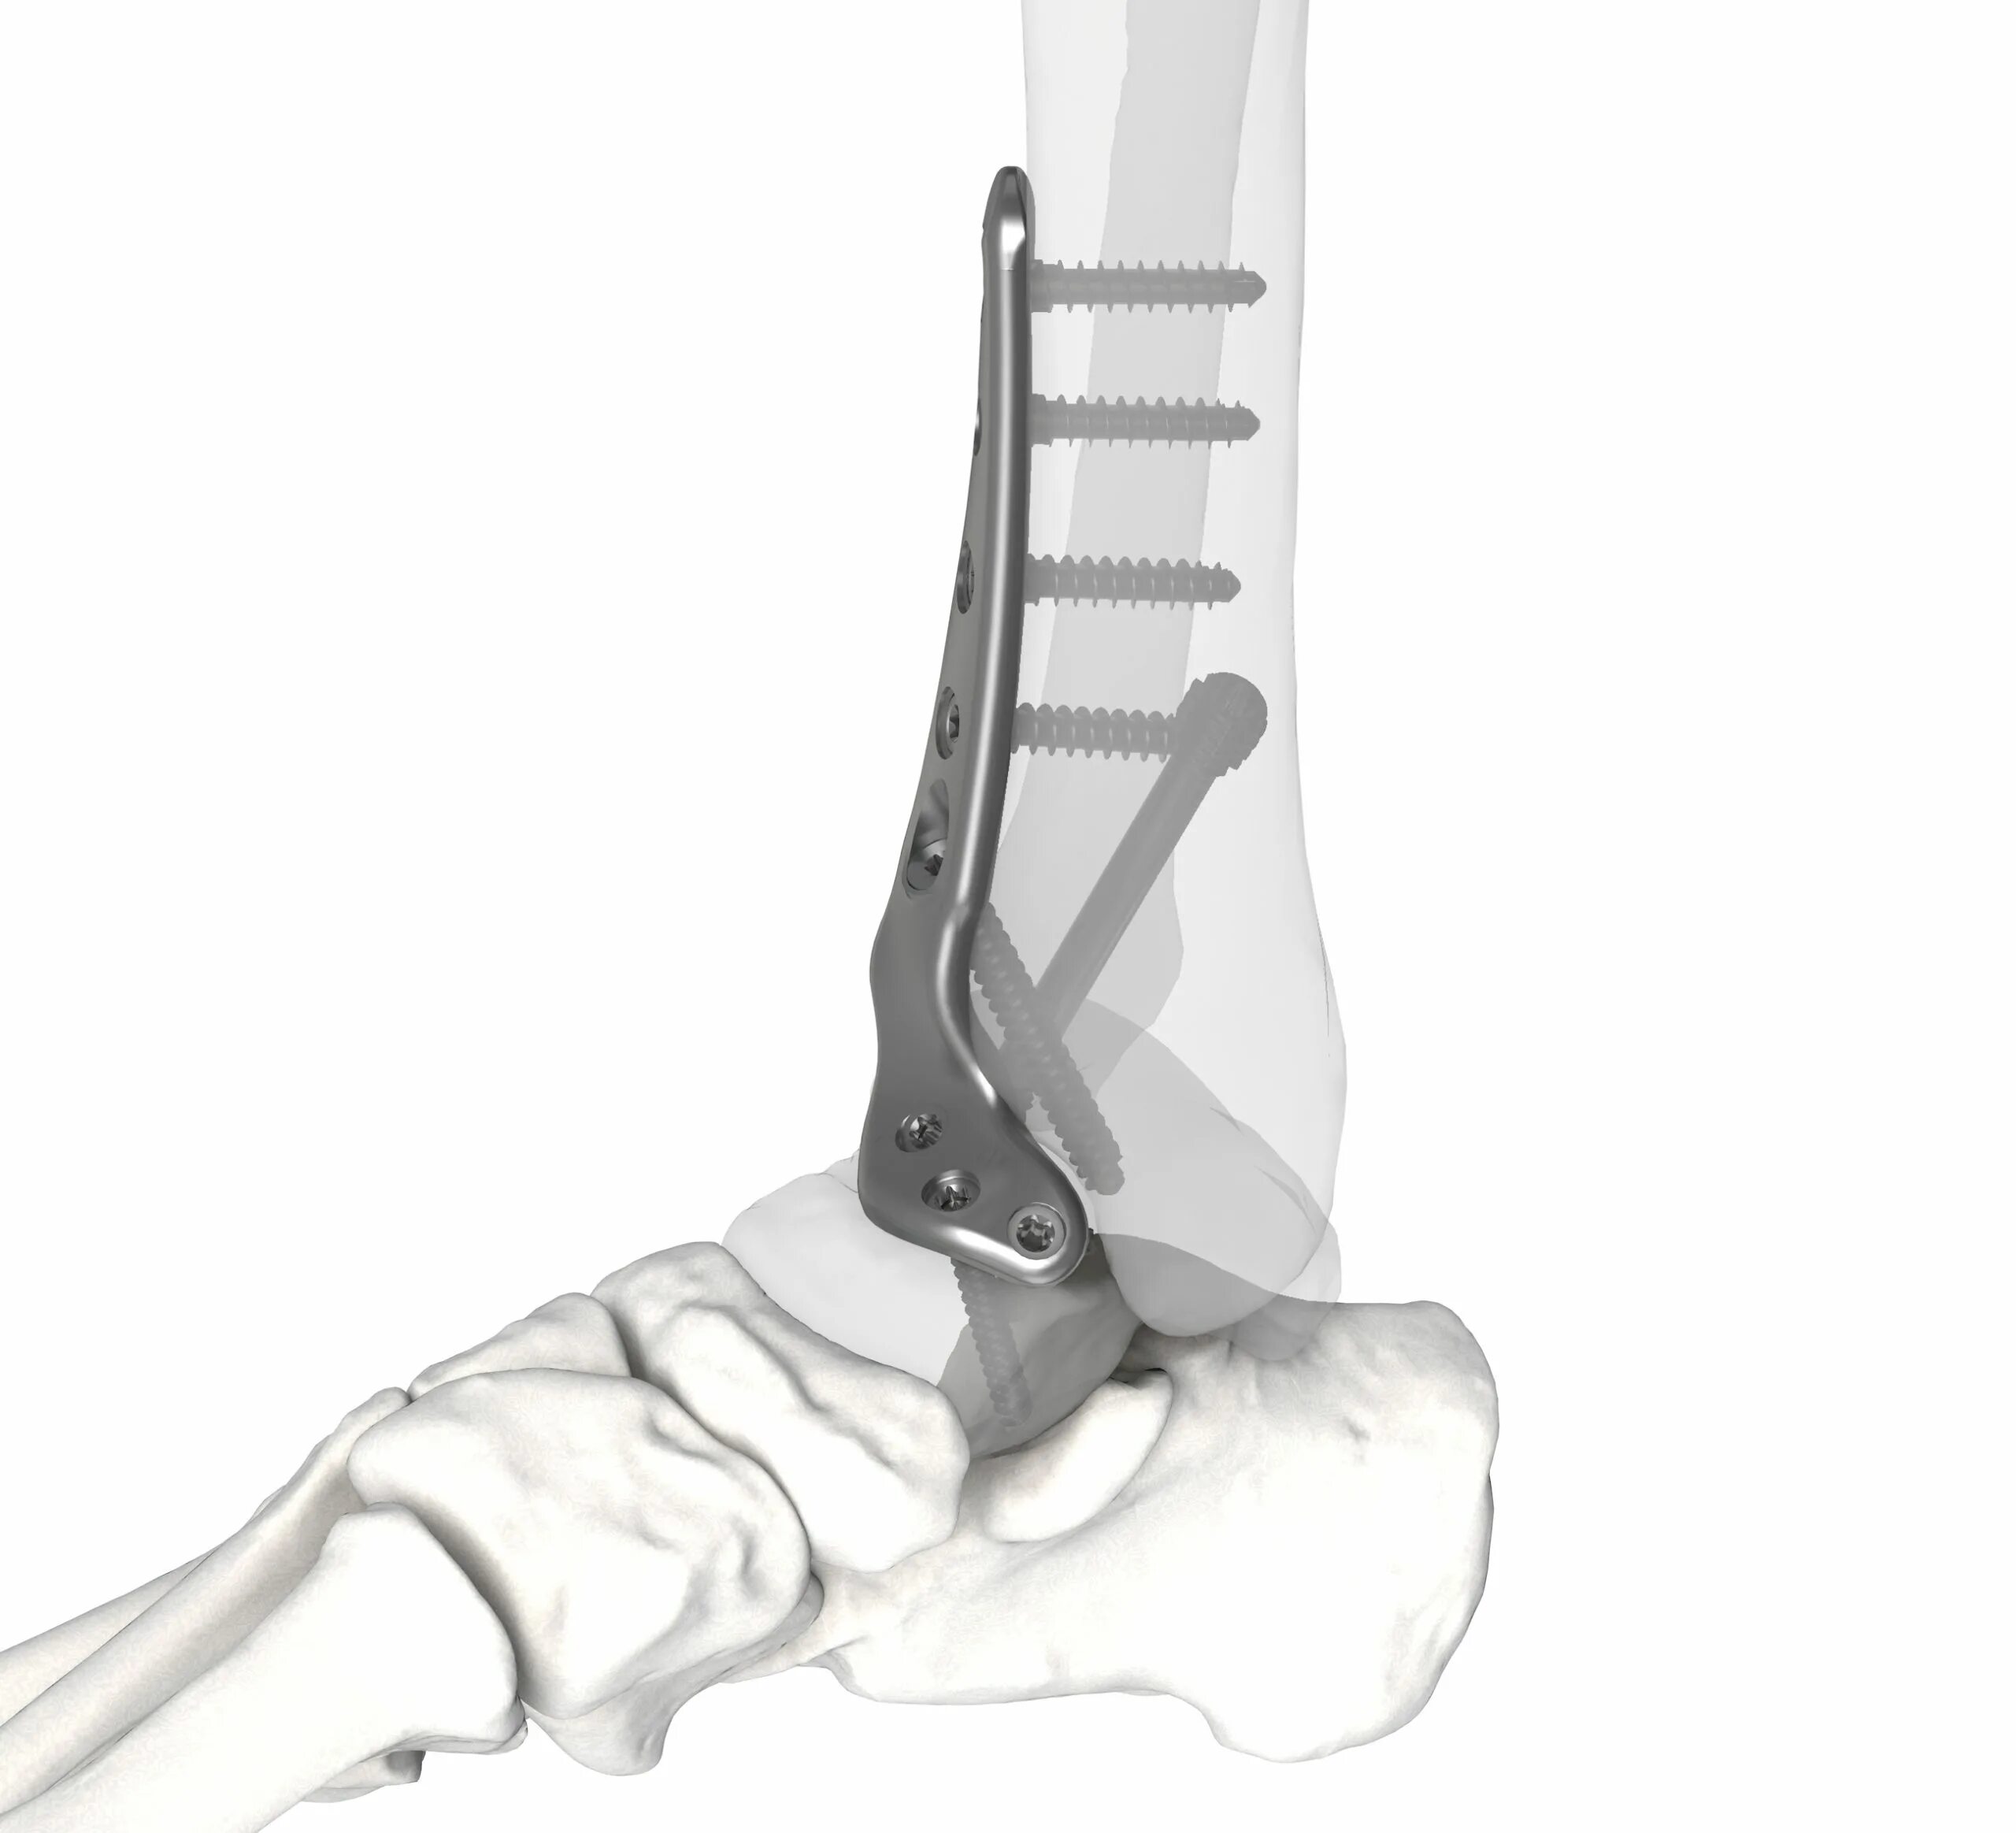

Артродез форум